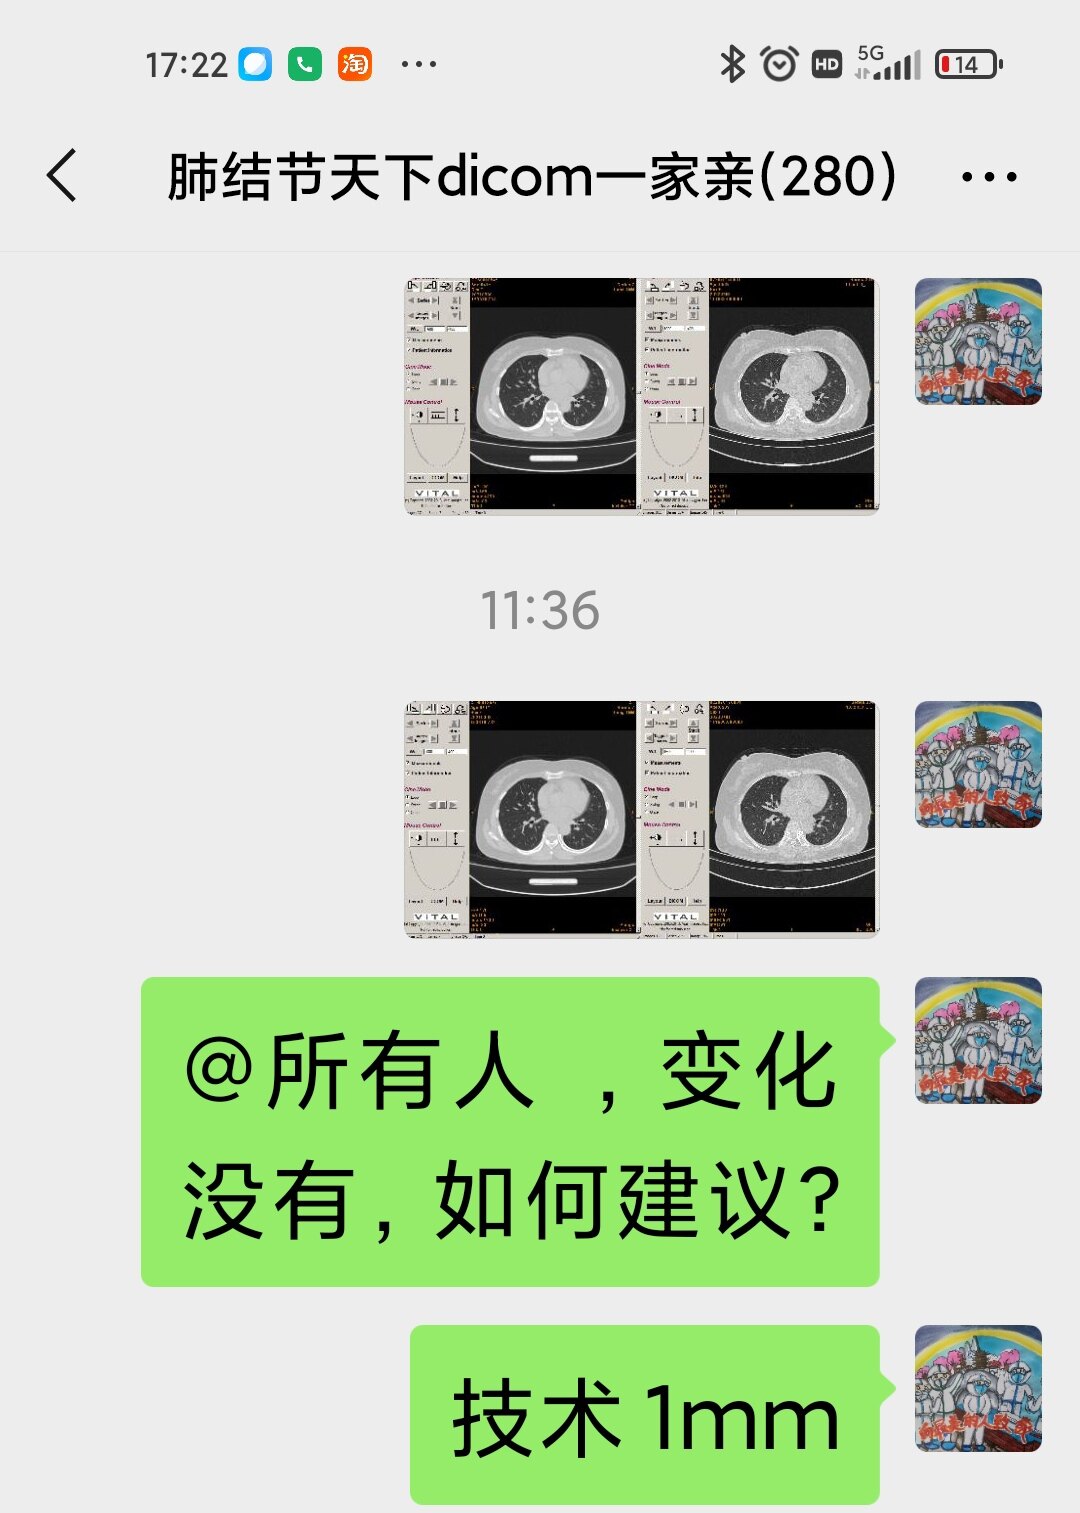

只言片语 之 (7)